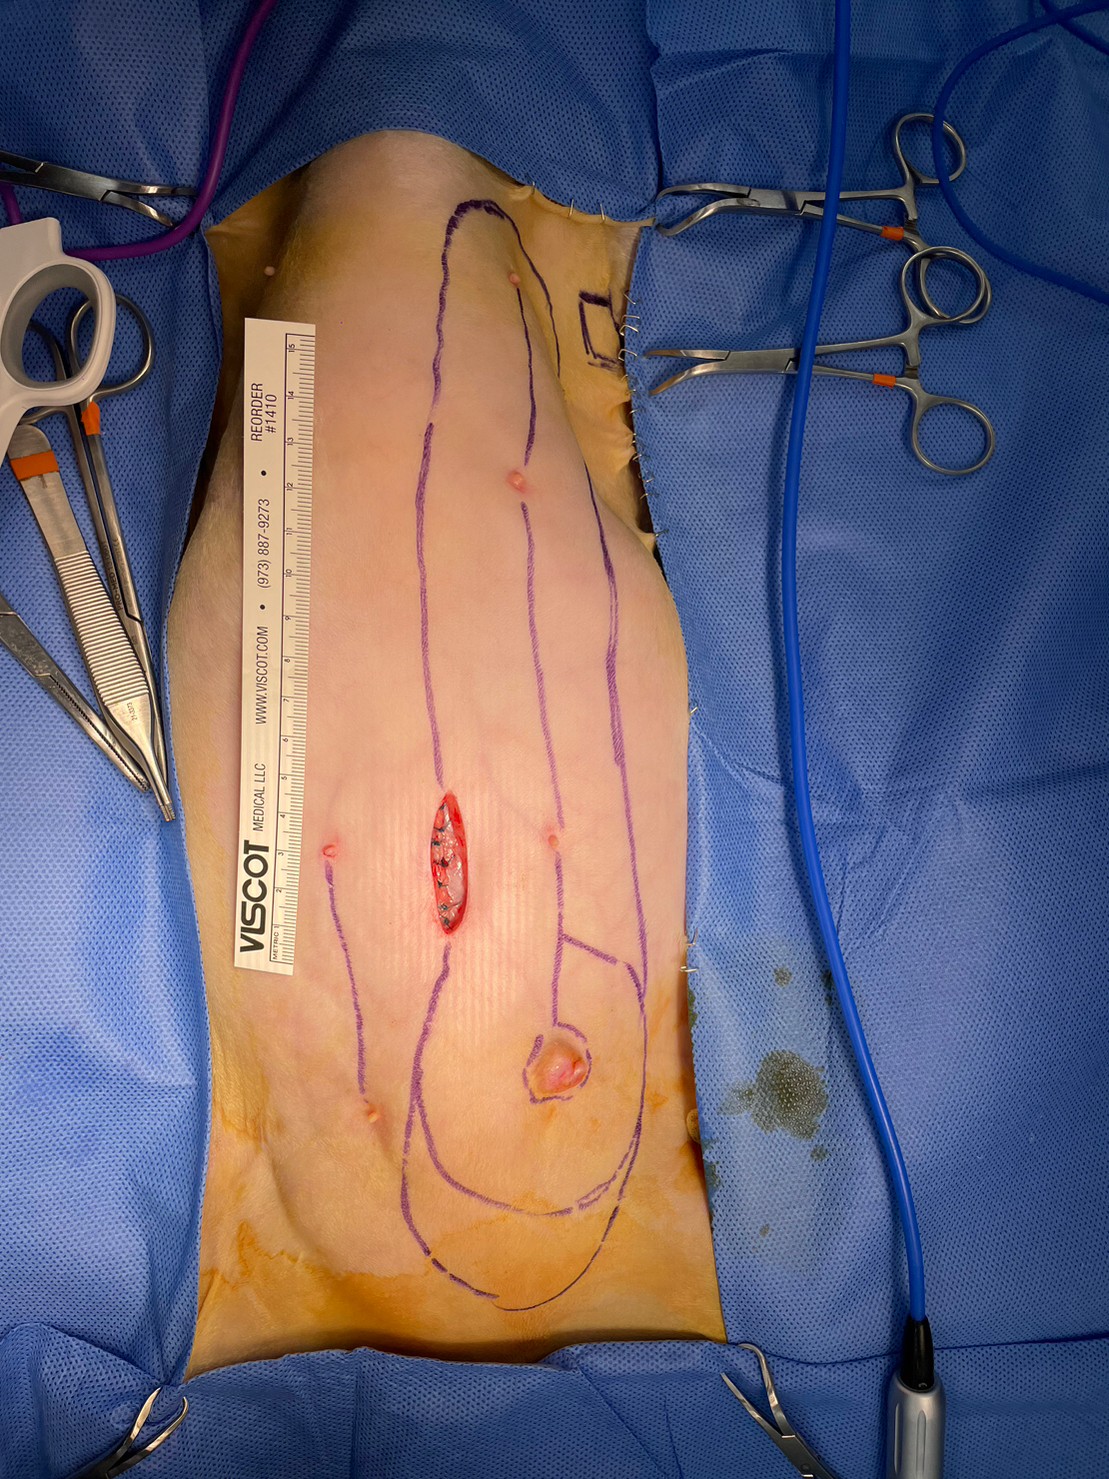

肚臍上有一道2公分長的傷口,是我們先花15分鐘做完的子宮卵巢摘除的術區,子宮很厚且裡面都是積液,我認為將其移除是正確的。

接著即將進行左側全乳腺切除術。